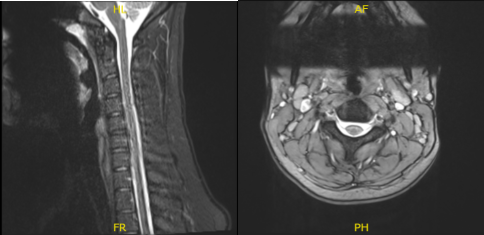

X Ray of Spine and left shoulder were presented during the visit, cervical spine X-ray showed an abnormal straightening cervical curve however left shoulder showed normal radiographs. In this follow up, I advised the patient to continue taking ibuprofen and an MRI will be presented the following week.

After a week patient returned with MRI result and showed that cervical spine showed significant result of straightening of the normal cervical lordosis, consistent with an element of muscle spasm and shoulder MRI showed tear of the superior glenoid labrum extending into the anchor the long head the biceps tendon.

MRI-3T Cervical Spine Non-contrast